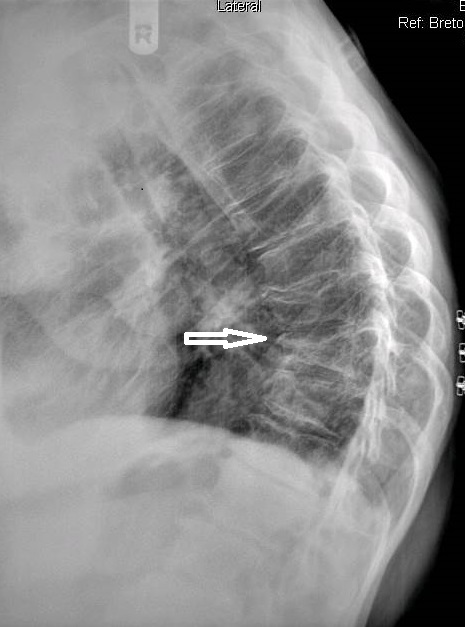

The chest series was obtained and again demonstrated the lesion noted previously on the thoracic spine. The lesion is more clearly seen on figure 3, the PA chest projection.  It measured 3.0 cm in the long axis, and the border was not particularly sharp and appeared somewhat spiculated on close inspection (open arrow points to lesion). No calcifications were noted within the lesion. This finding is worrisome, as benign granulomatous lesions, which are often discovered incidentally, frequently manifest some degree of calcification, while more aggressive lesions exhibit calcification less often. Figure 4 again demonstrates the thoracic spine compression fractures.